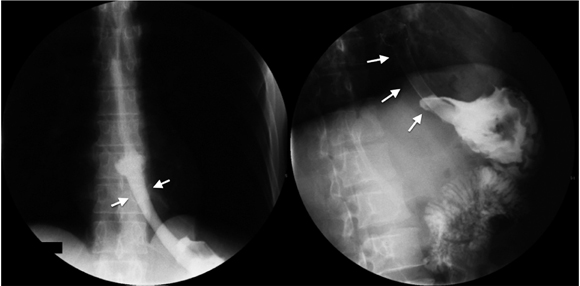

Tumores malignos de esófago

El cáncer de esófago es una patología cada vez más frecuente, con tasas de supervivencia desalentadoras, y su localización nos sugiere el tipo histológico (esófago medio y superior, generalmente escamocelular, y esófago inferior -adenocarcinoma, en su gran mayoría-). El esofagograma, además de permitir localizar el tumor y ayudarnos a generar un plan quirúrgico, nos da una idea de su estadio (los tumores con una longitud mayor de 5 cm y los tumores estenosantes generalmente corresponden a tumores T3 y T4) 28,29 (Figura 10). La sensibilidad del estudio es mayor al 95 % para el diagnóstico de cáncer de esófago, similar a la sensibilidad de la endoscopia digestiva (95% al 100%) (10).